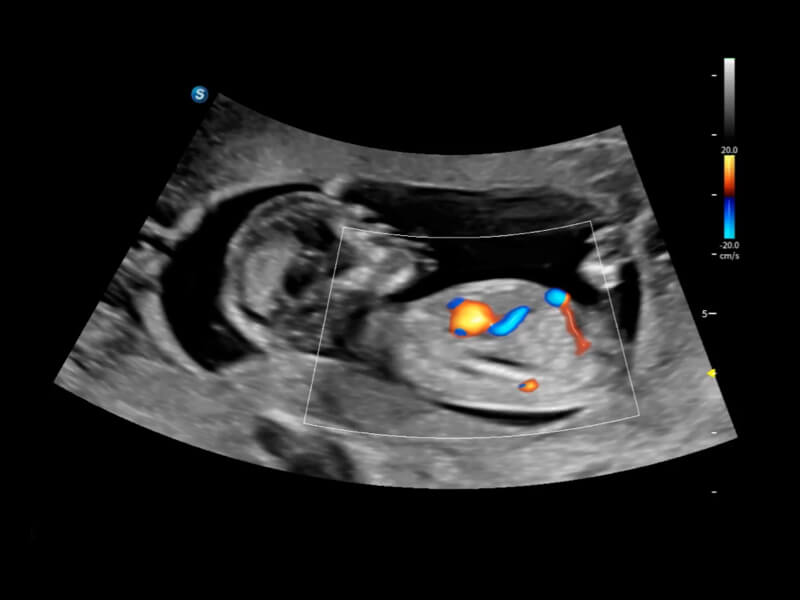

Fine-tuned Hemodynamic Solution

A wide variety of hemodynamic diagnostic techniques enable effective blood flow signal detection across different scenarios.

• FHR

FHR enables the observation of microvascular structure within organs with enhanced sensitivity and improved resolution, ensuring the precision in representing the actual state of blood circulation.

• Bright Flow

Bright Flow offers 3D-like color Doppler flow visualization without requiring a volume transducer, thereby strengthening the boundary definition of vessel walls.

• Micro F

Micro F efficiently distinguishes subtle blood flow signals from overlaying tissue motion, enabling heightened sensitivity and spatial resolution in hemodynamic depiction.